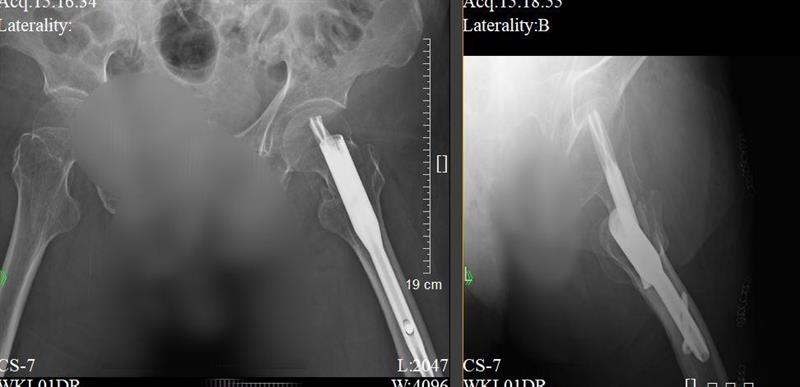

“高齡不是手術禁區,關鍵在于精準評估與高效協作。”南方醫院創傷骨科陳濱主任提到。南方醫院創傷骨科髖關節外科醫師團隊接診這位患者后,立即啟動醫院老年髖部骨折急診綠色通道,同步啟動MDT會診機制,聯合麻醉科、心血管內科、康復醫學科等專家迅速對患者心肺功能、認知狀態、手術耐受性進行全面研判,最終確定“腰麻下閉合復位PFNA內固定術”方案——這種微創技術通過3個不足3cm的切口即可完成骨折固定,能最大程度減少軟組織損傷,為早期康復奠定基礎。在創傷骨科陳濱主任和胡稷杰教授指導下,李凱群主治醫師在新型三維C臂機精準引導下,僅用20分鐘便完成骨折閉合復位與髓內釘固定。

患者術后骨折X光片